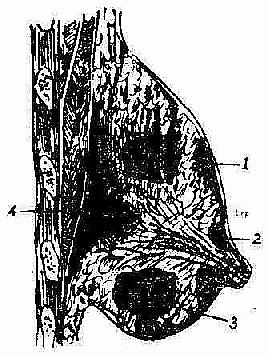

急性乳房炎脓肿形成期,治疗要则是及时切开引流,排出积脓。切开引流应注意如下要点:(1)为避免手术损伤乳管而形成乳瘘,切口应按轮辐方向作放射状切开,至乳晕处为止;深部脓肿或乳房后脓肿,可沿乳房下缘作弧形切口,经乳房后间隙引流之;既可避免乳管损伤,亦有利于引流排脓。乳晕下脓肿,应作沿乳晕边缘的弧形切口。(2)若炎症明显而未见波动处,不应消极等待,应在压痛最明显处进行穿刺,及早发现深部脓肿。(3)脓肿切开后,应以手指深入脓腔,轻轻分离其间的纤维间隔以利引流彻底。(4)为使引流通畅,可在探查脓腔时,找到脓腔的最低部位,别加切口作对口引流。(图2-12,2-13,2-14)。

图2-12乳房脓肿的不同部位

1. 表浅脓肿 2. 乳晕下脓肿

3. 深部脓肿 4. 乳房后脓肿